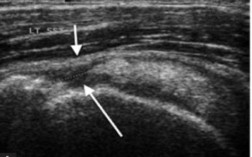

Siêu âm.

Có độ nhạy và độ đặc hiệu lớn hơn 90% theo các báo cáo ở nước ngoài.

Chưa có công trình nghiên cứu trong nước công bố độ nhạy và độ đặc hiệu.

Hình ảnh dịch trong khoang dưới MCV và dưới mỏm quạ, hình ảnh viêm túi hoạt dịch dưới MCV, viêm gân CX, rách gân chóp xoay, viêm đầu dài gân nhị đầu.

Hình 1.23. Hình minh họa trên siêu âm, mũi tên màu trắng cho thấy hình ảnh rách gân trên gai hoàn toàn52.